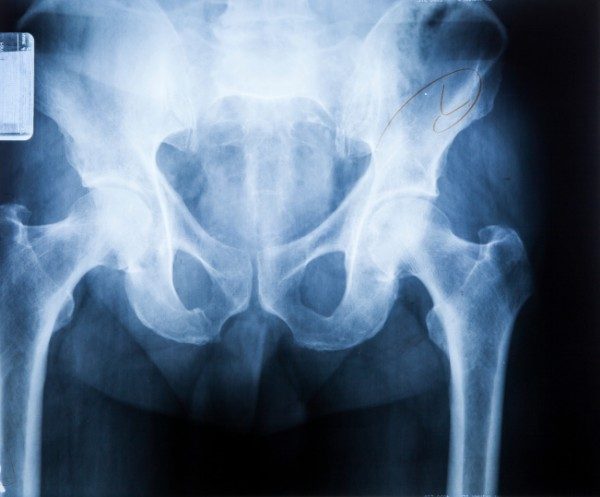

Esistono diversi tipi di anca a scatto che può definirsi interna o esterna. Tutto dipende dal tipo di movimento, muscoli, e articolazioni coinvolte. Nella maggior parte dei casi, lo scatto è provocato dal movimento di un muscolo o di un tendine sopra una struttura ossea nell’anca. Il punto più comune dove si può manifestare questo problema è l’esterno dell’anca in cui una banda di tessuto connettivo nota come “banda iliotibiale” passa sopra una parte del femore che sporge (il grande trocantere). In posizione eretta la banda si trova dietro il trocantere. Quando si piega l’anca, tuttavia, il gruppo si può spostare in avanti, di fronte al trocantere. Ciò può causare il rumore.

Anche il tendine ileopsoas, che collega la parte interna della coscia, può scattare con un movimento dell’anca.

Un altro sito di aggancio è nella parte superiore del femore, quella a sfera che si inserisce nella presa del bacino per formare l’articolazione dell’anca. Lo scatto avviene quando il tendine femorale retto, che si estende dall’interno del femore attraverso il bacino, si muove in avanti e indietro quando l’anca si piega o si addrizza, il tutto proprio all’altezza della parte sferica.